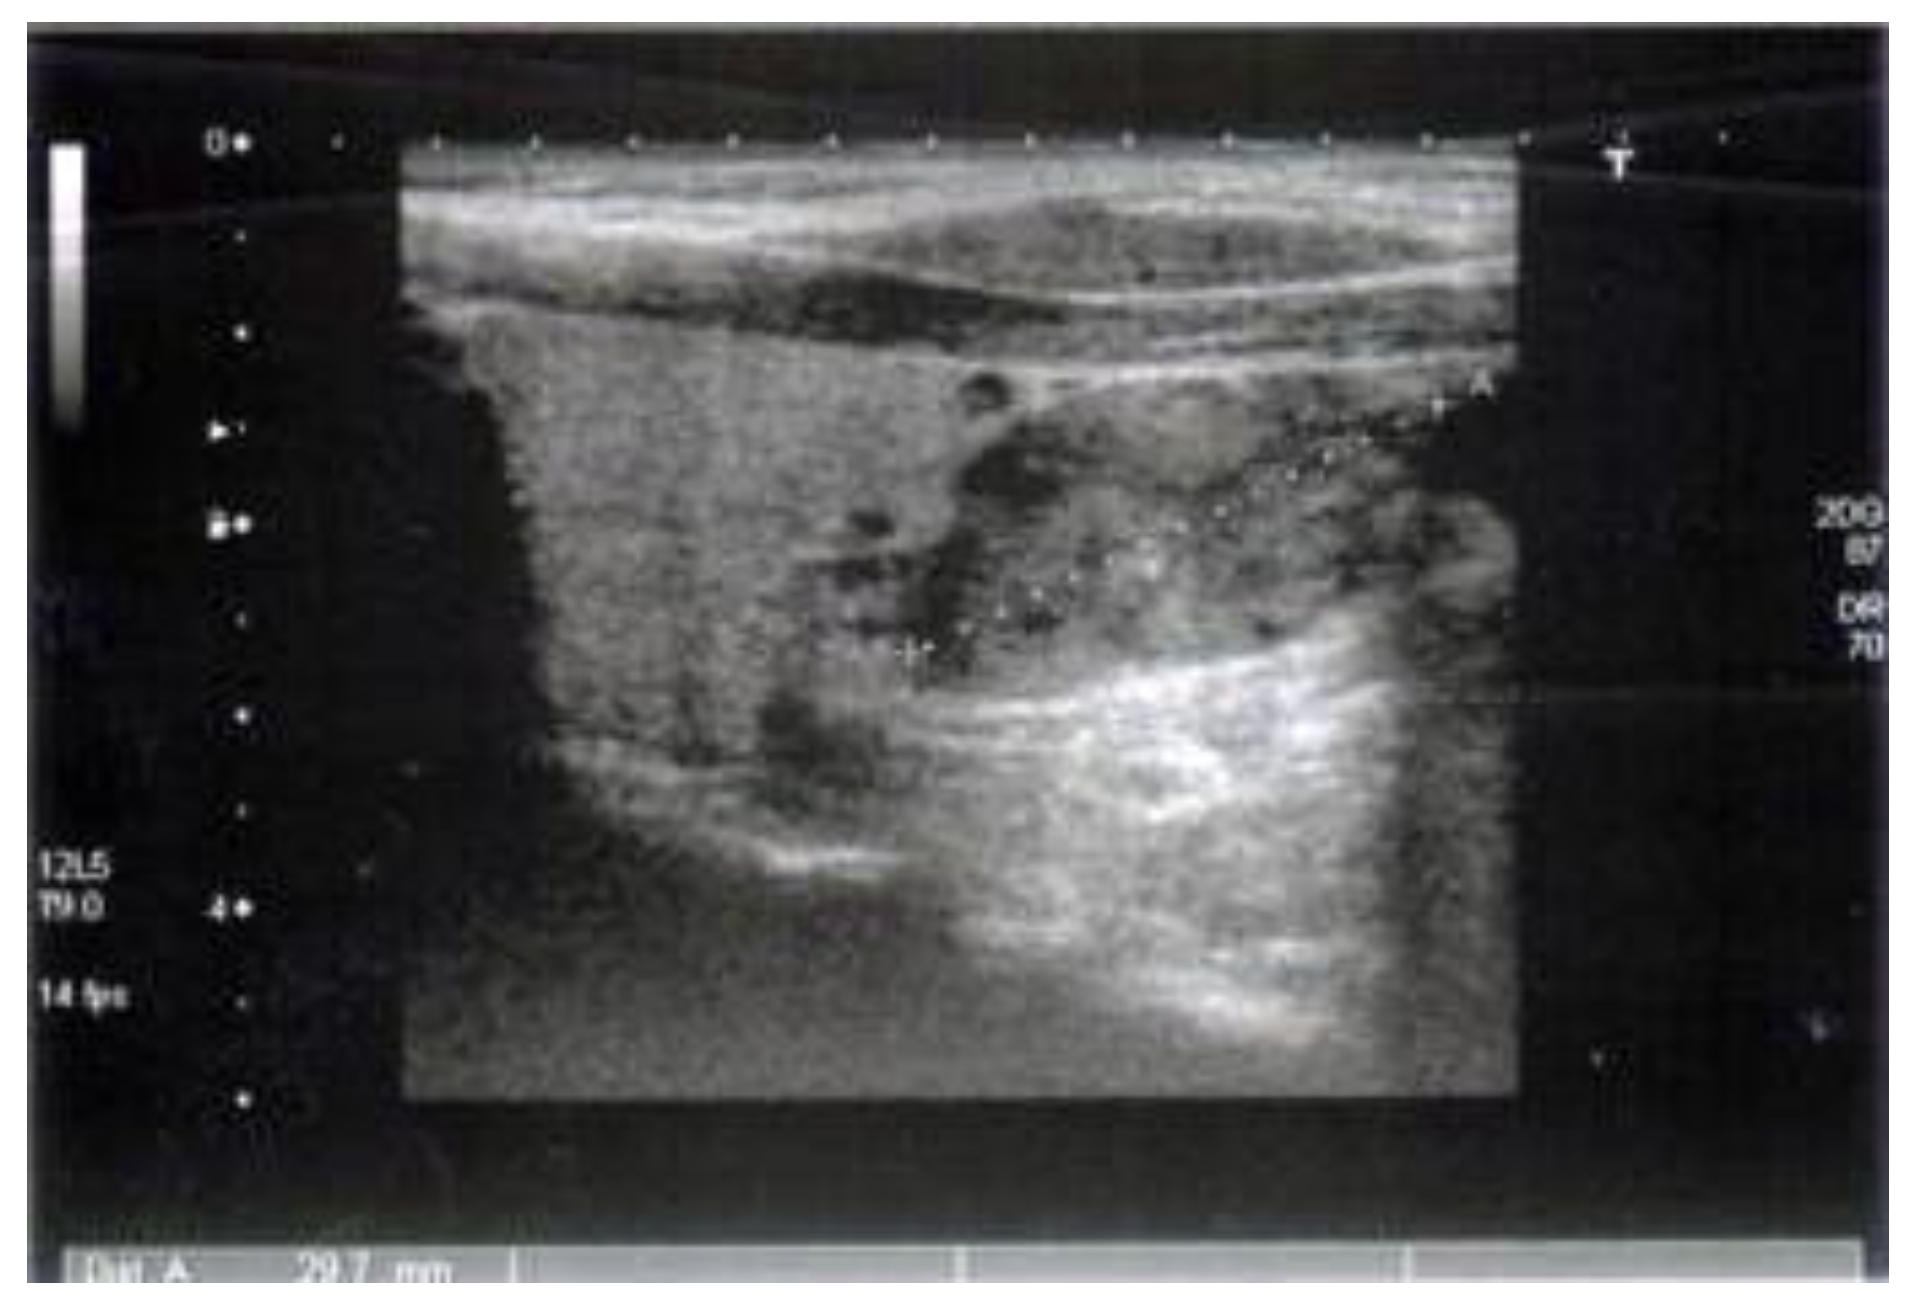

A 52-year old Caucasian man was diagnosed with chronic recurrent pancreatitis in 2007. The diagnosis was based on personal pathological history (repeated episodes of acute pancreatitis, biochemical, and imagistic investigations). A suggestive aspect of chronic pancreatitis evidenced by cholangio nuclear magnetic resonance is shown in Figure 1, Figure 2, Figure 3.

The first episode of acute pancreatitis occurred in 2002 when the patient was hospitalized in an emergency department with intense pain in the epigastrium with dorsal irradiation after a high-fat meal. Upon admission, the patient had elevated values of serum amylase (817 U/l: normal range: < 100 U/l) and leukocytosis. The abdominal ultrasound revealed a slightly enlarged pancreas, non- homogeneous echotexture, and the absence of intra or extra pancreatic collections. The evolution was favorable under conservative treatment, with symptomatic remission and normalization of serum amylase levels. In October 2004, the patient returned to the emergency department with the same symptomatology. Paraclinical investigations revealed leukocytosis, serum amylase values of 1.300 U/l, and fluid in the peritoneal cavity without visible collections. Conservative treatment (antispastics, antisecretory drugs, anti-enzymatic drugs, antibiotics) led to improvement of the clinical symptomatology. In November 2004, an endoscopic retrograde cholangio pancreatography was performed, which established the diagnosis of stenotic papillomatosis. Papilosfincterectomy was performed with a stent mount that was removed one month later. In 2005, the patient underwent a surgical intervention for chronic lithiasis, and cholecystectomy was performed. In 2007, the patient presented 3 episodes of acute pancreatitis. The imaging investigations (computerized tomography and nuclear magnetic resonance) highlighted the presence of multiple intraductal calculi, and for this reason the extraction of calculi was performed with papillotomy and stenting (which had to be changed every 6 months). Additional investigations on the etiology of recurrent chronic pancreatitis, initially diagnosed as idiopathic, revealed elevated values of total serum calcium (2.90 mmol/l, 2.99 mmol/l; normal range: 2.10-2.65 mmol/l) and serum parathormone (448.8 pg/ml; normal range 15.0-68.3 pg/dl). The presence of a parathyroid adenoma in the right lower pole of the thyroid was subsequently highlighted through ultrasound (Figure 4 and 5) and subsequently by scintigraphy. In September 2007, a parathyroidectomy was performed. In February 2008, the imaging control and the laboratory tests (after surgery) were performed. The values of total serum calcium were 2.49 mmol/l, serum parathormone 112 pg/ml, and thyroid scintigraphy (after the intravenous administration of 74 Mega-Becquerel Technetium 99 m) highlighted the homogenous distribution of the radioactive tracer without hot or cold areas. After parathyroidectomy, the patient showed a favorable evolution with the remission of the acute episodes of pancreatitis. The patient did not have any family history of diabetes. However, in 2017, he was diagnosed with diabetes. From the personal pathological history, the patient has been diagnosed with renal bilateral lithiasis with repeated eliminations of calculi.

Figure 4. Inferior parathyroid adenoma located between the carotid-tracheal-cross section.